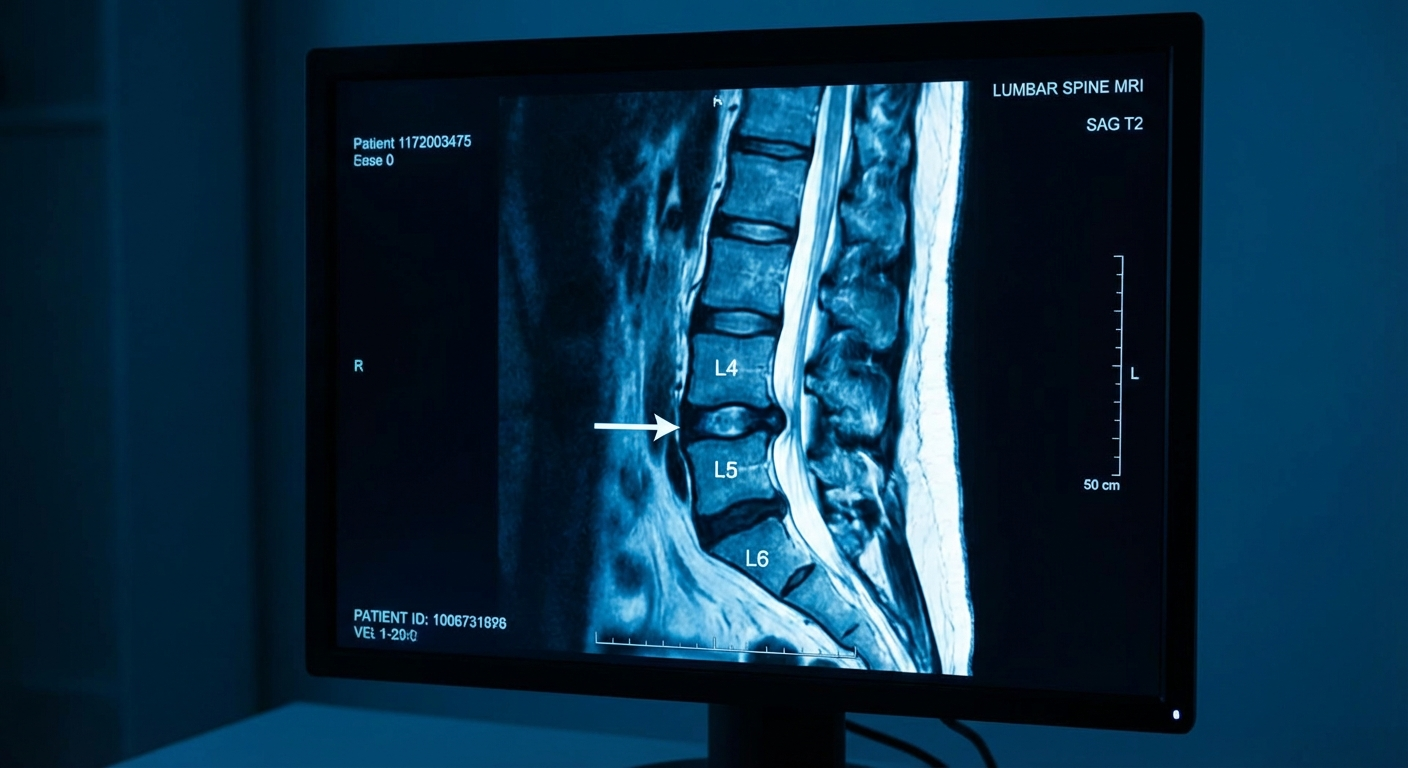

The sciatic nerve is formed by nerve roots from the L4, L5, S1, S2, and S3 levels of the spine. The specific nerve root affected determines the exact pattern of pain, numbness, and weakness experienced.

- MRI of the lumbar spine β identifies disc herniations, stenosis, and other structural causes with high accuracy. Recommended when symptoms are severe, progressive, or not responding to conservative treatment after 4β6 weeks

Important caveat: MRI findings must be correlated with clinical symptoms. Research consistently shows that up to 30% of asymptomatic adults have disc herniations visible on MRI (Brinjikji et al., 2015). An MRI finding alone does not confirm that a disc herniation is causing your pain.